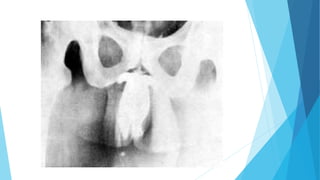

 La cavernografía es un estudio contrastado para detectar la presencia de

drenaje venoso y el estudio anatómico de los cuerpos cavernosos y esponjosos

del pene por medio de la inyección de M.C. hidrosoluble en la base del

mismo.

 Debe realizarse con el estado del pene flácido y erección inducida

farmacológicamente (papaverina) o mediante una bomba de erección

artificial. Nos muestra con certeza si hay o no sistema de drenaje

inadecuados y alteraciones anatómicas de los cuerpos cavernosos del pene,

como en la enfermedad de Peyronie.